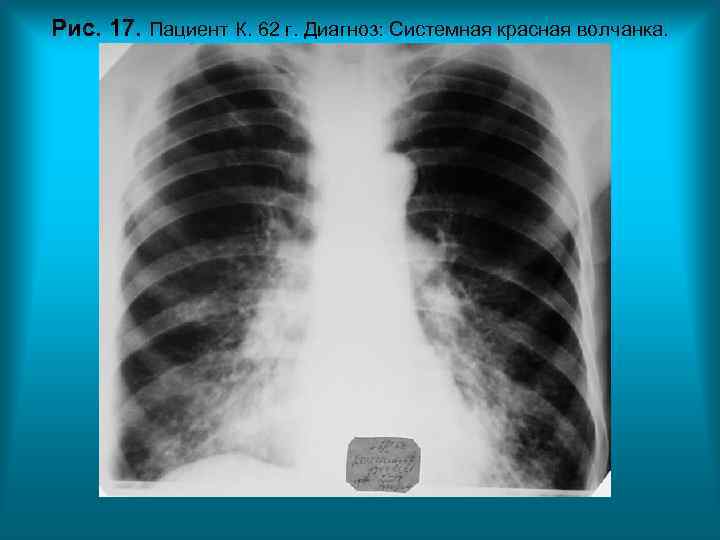

Рис. 17. Пациент К. 62 г. Диагноз: Системная красная волчанка.